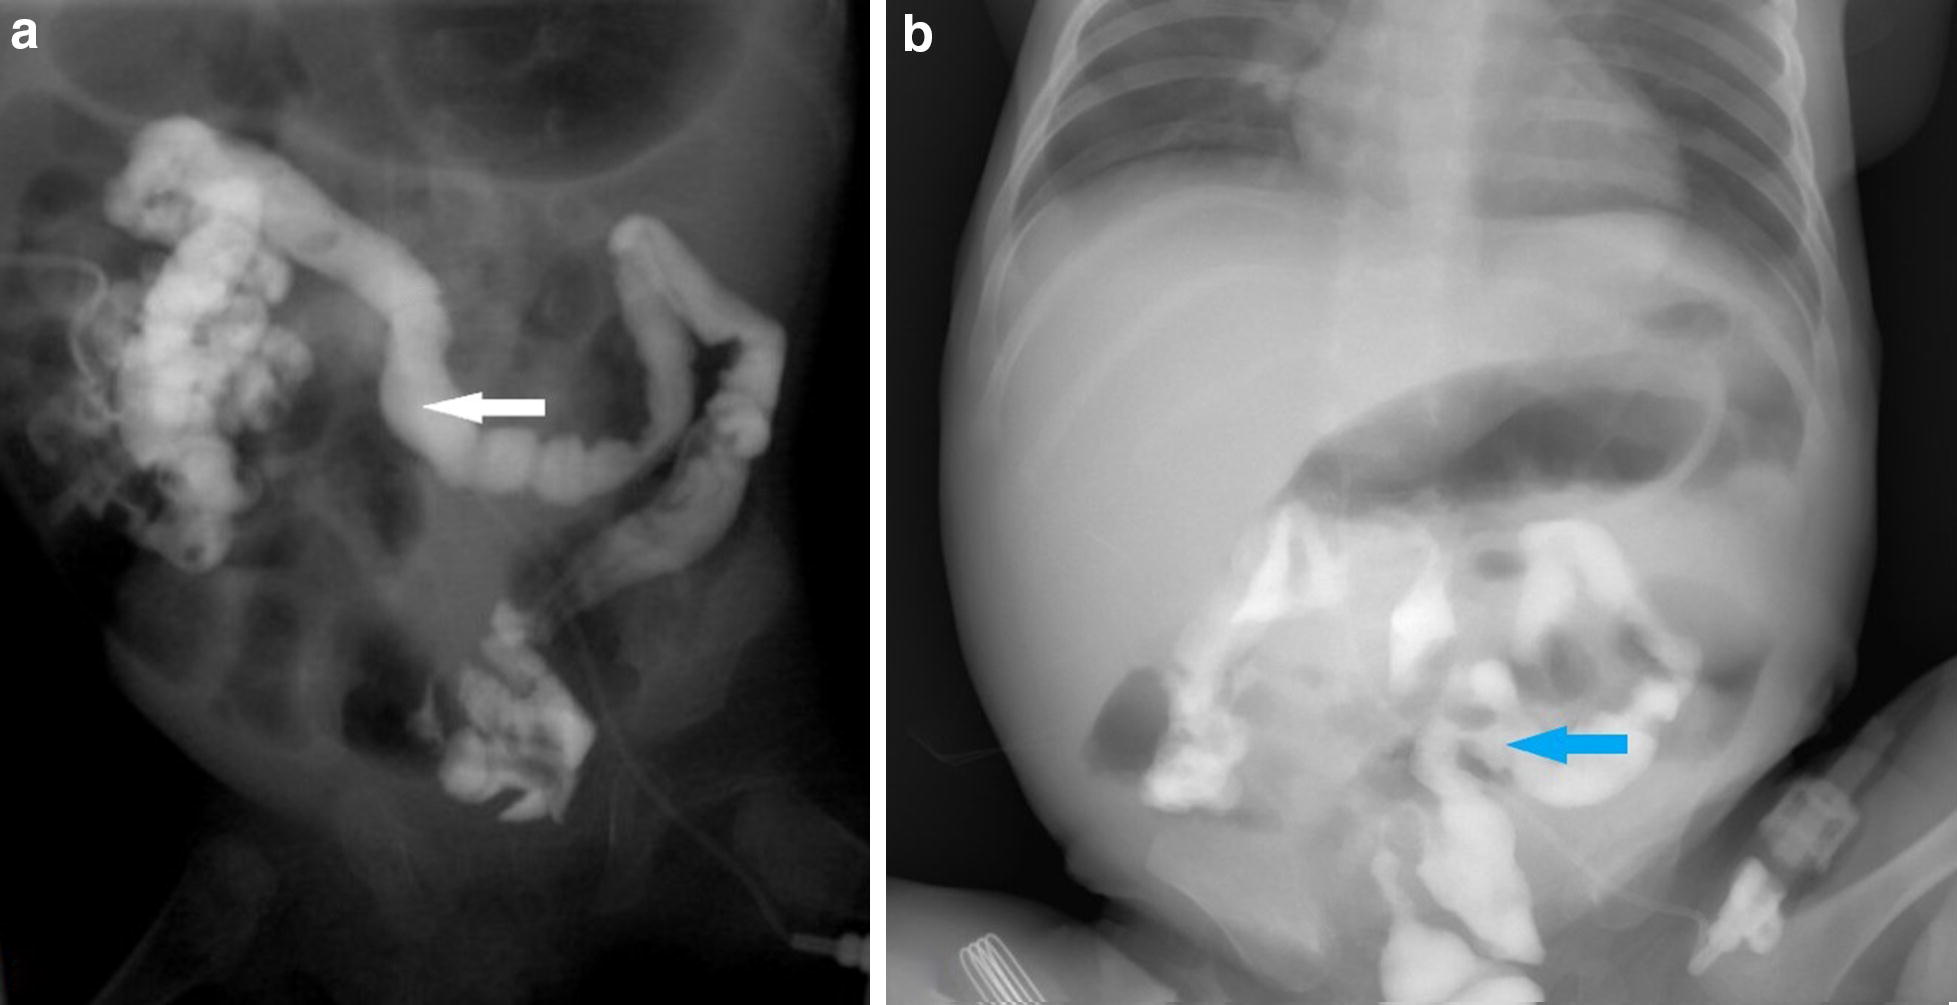

After the infant started receiving feeding, he suffered from a relapsing infection. WBC count and CRP level increased to 28.9 × 109/l and 156 mg/l, respectively. The temperature, WBC, and CRP returned to an acceptable range as vancomycin and meropenem (20 mg/kg, Q8 h) were given. A colonoscopy was performed on the infant, which indicated the smooth intestinal mucosa and clear intestinal wall vessels (Fig. 1). A distal stoma imaging was also performed on the infant, which revealed a rigid lumen from the transverse colon to the descending colon (Fig. 2).

Fig. 2.

a The distal stoma imaging. The maximum width of the transverse colon was approximately 0.8 cm (the white arrow). b The upright plain abdominal radiograph. The image was taken 24 h after the previous imaging. The contrast medium was stranded in the colon (the blue arrow)